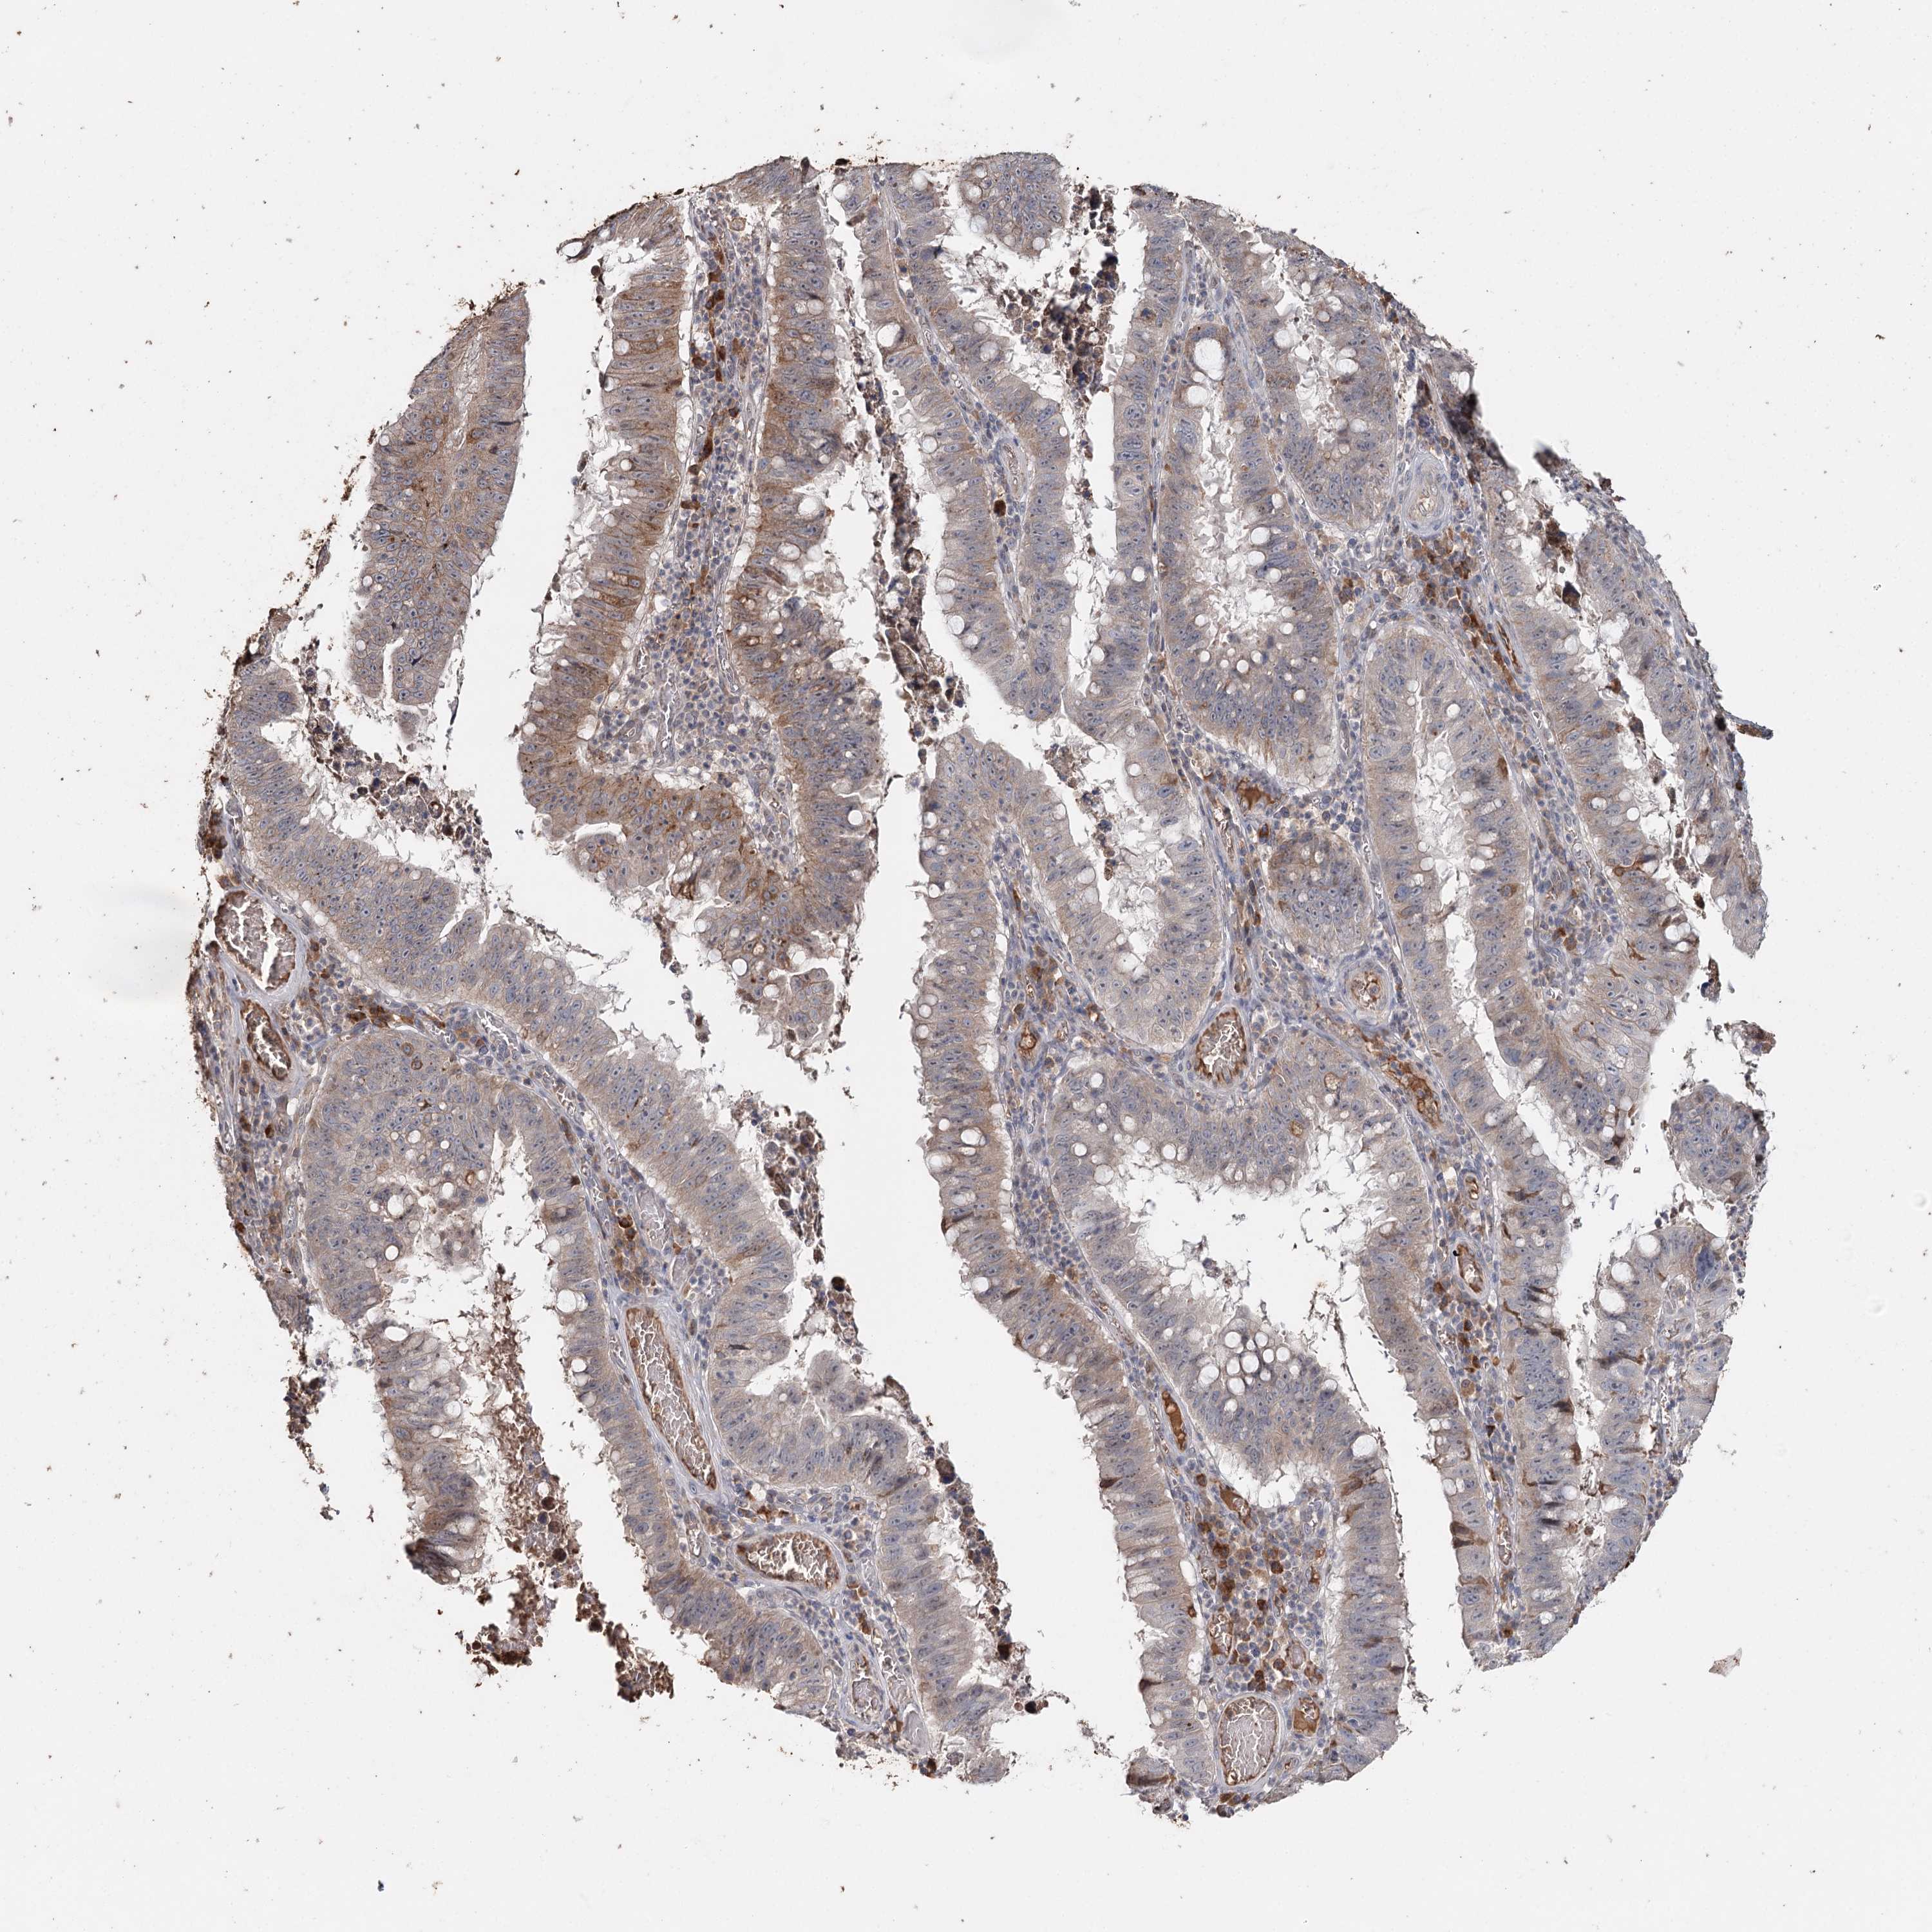

STOMACH CANCER - Protein expressioni

A mouse-over function shows sample information and annotation data. Click on an image to view it in a full screen mode. Samples can be filtered based on level of antibody staining by selecting one or several of the following categories: high, medium, low and not detected. The assay and annotation is described here.

Note that samples used for immunohistochemistry by the Human Protein Atlas do not correspond to samples in the TCGA dataset.

Antibody stainingi

Antibody staining in the annotated cell types in the current human tissue is reported as not detected, low, medium, or high, based on conventional immunohistochemistry profiling in selected tissues. This score is based on the combination of the staining intensity and fraction of stained cells.

Each image is clickable and will lead to virtual microscopy that enables deeper exploration of all samples and also displays staining intensity scores, fraction scores and subcellular localization as well as patient and tissue information for each sample.

Antibody HPA005480

Antibody HPA024300

Antibody CAB037030

Staining

High

Medium

Low

Not detected

Intensity

Strong

Moderate

Weak

Negative

Quantity

>75%

75%-25%

<25%

None

Location

Nuclear

Cytoplasmic/membranous

Cytoplasmic/membranous,nuclear

Adenocarcinoma, NOS

Adenocarcinoma, High grade